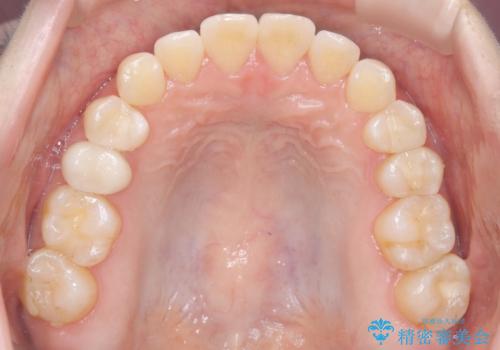

前歯と奥歯のガタガタを矯正で改善

- 患者様は、前歯と奥歯のガタガタ(叢生)を改善し、正面から見た時の歯並びを美しく整えたいとのご要望で来院されました。診断の結果、非抜歯での矯正が可能と判断し、インビザラインを使用する治療計画を立案しました。透明な矯正装置で目立ちにくい治療を行いながら、前歯と奥歯の両方を整列させることを目標にしました。

インビザラインを用いて、前歯の見た目を重視しつつ、奥歯のガタガタも改善しました。特に正面から見た際の美しい歯列を意識し、段階的に歯を移動させることで、全体の調和を図りました。治療中は、適切な装着時間を守ることや、装置の清潔を保つことが重要でした。また、歯肉や歯列全体に無理な負担がかからないように移動を管理しながら治療を進めました。結果として、前歯と奥歯がきれいに並び、見た目にも機能的にも満足いただける仕上がりとなりました。